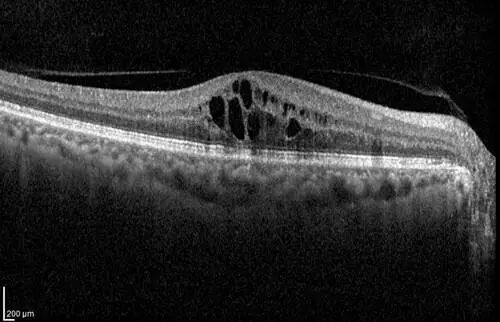

发病时: 黄斑区囊样水肿,视网膜显著增厚。

手术前:黄斑区可见牵拉性前膜,视网膜结构扭曲,伴有黄斑水肿。

治疗前后黄斑区视网膜厚度对比:因黄斑水肿明显消退,视网膜厚度值明显降低。

治疗前